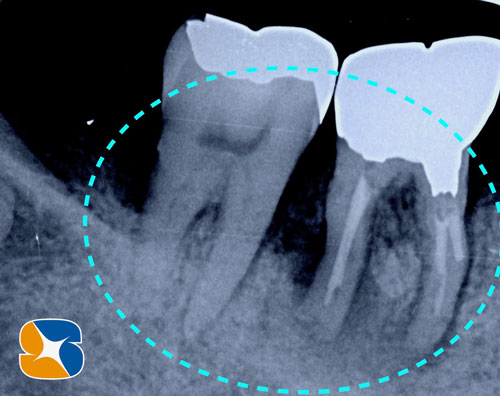

左下のインプラント予定部。

切開して開けてみると、2ヶ月前の抜歯跡が見受けられた。しかし

当院では骨の再生治療をインプラント移植時に同時進行で施しているので、全く問題はありません。

骨のない所に人工骨のβ–TCPを添加して、本物の骨に置換するのを待ちます。